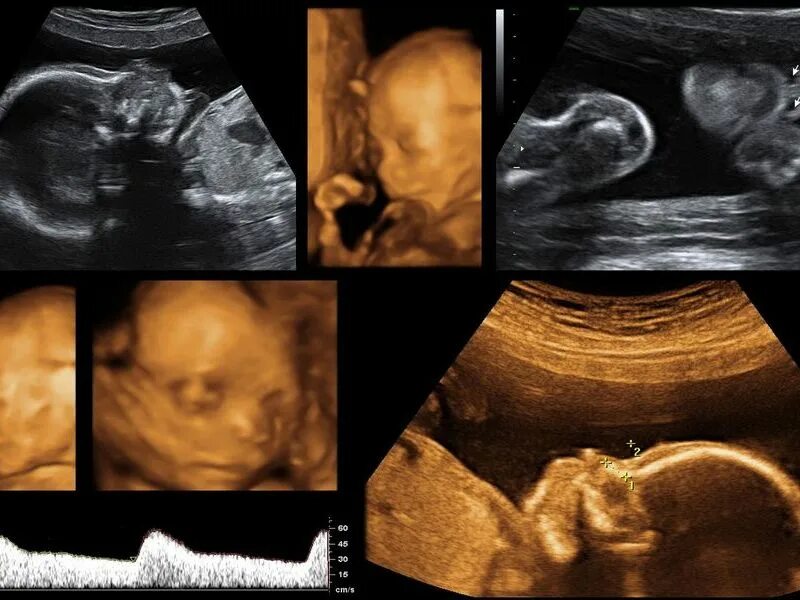

Скрининг 2025 год